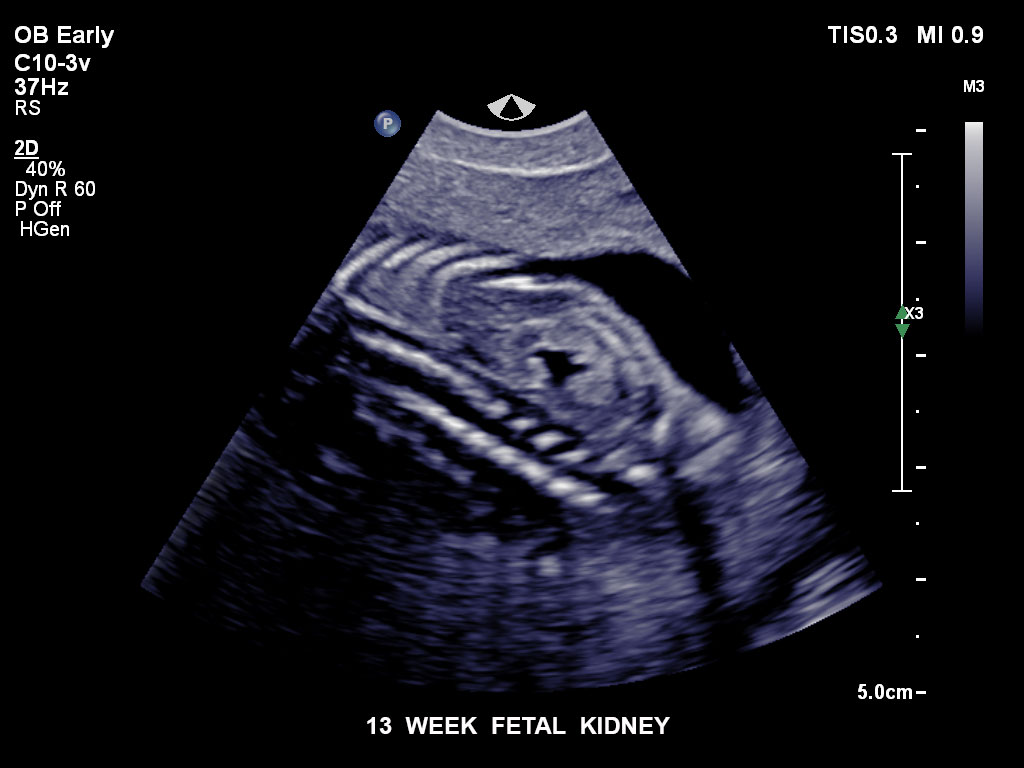

• C9-2 PureWave-Breitband-Convex-Schallkopf für Hochfrequenz-Bildgebung in der Gynäkologie und der Geburtshilfe, insbesondere für die Untersuchung im Hinblick auf mögliche Anomalien im ersten Schwangerschaftstrimester

• C10-3v PureWave-Breitband-Endo-Convex-Schallkopf, ideal für anspruchsvolle Myom- und komplexe Ovar-Untersuchungen sowie Bildgebung im ersten Schwangerschaftstrimester